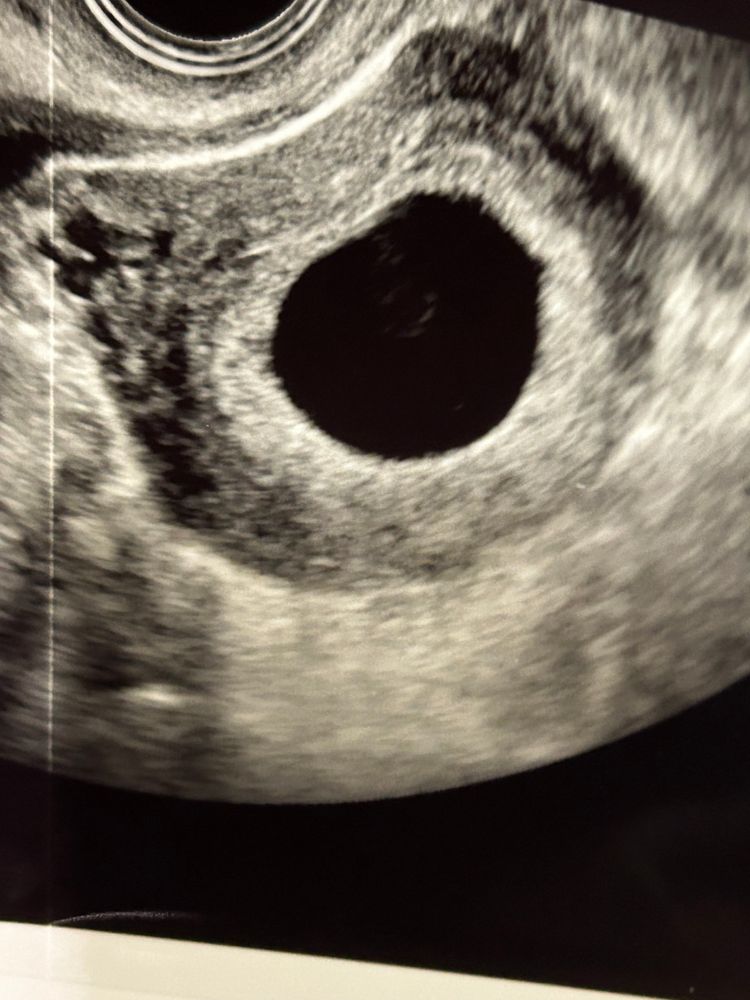

Что внутри плодного яйца ? 21 мм плодное , 6 нед 4 дня, ставят анембрионию